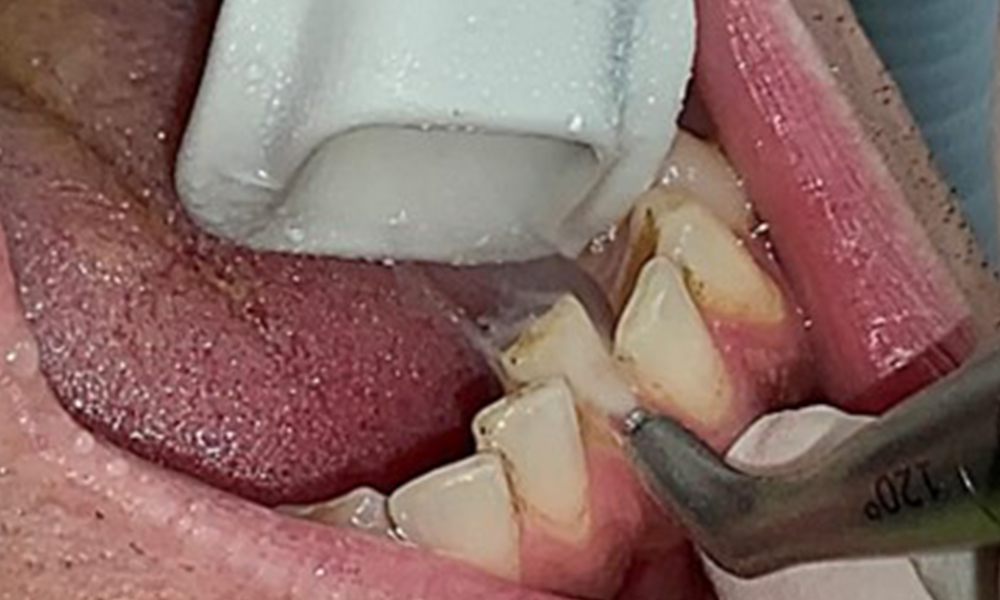

Поради иначе благоприятното общо медицинско състояние, нуждите, определени по време на оралния преглед, ще бъдат решаващи за лечението. От съществено значение ще бъде периодичното определяне на дълбочината на сондиране. Гингивалното кървене намалява при пушачите, поради което клиничната диагноза на пародонтита може да се постави само чрез сондиране (фиг. 7). Поставянето на изключителен акцент върху определянето на индексите на кървене може да замъгли съществуващ пародонтит или гингивит. (5)

Целта е да се контролира рискът от заболяване чрез отстраняване на супрагингивалния и субгингивалния биофилм. Инструментите трябва да бъдат подбрани въз основа на нуждите на пациента. Първо трябва да се отстранят зъбният камък и всички конкременти с помощта на ултразвукови и/или ръчни инструменти (фиг. 10).